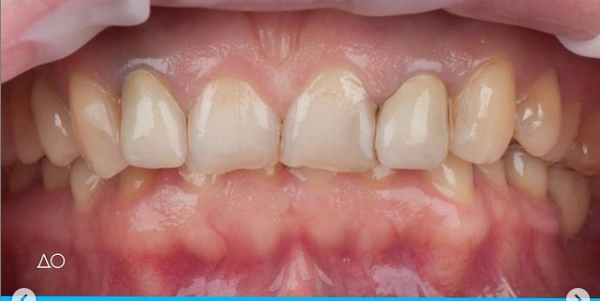

Установка керамической коронки

Изготовили и установили 22 керамические коронки EMAX и 6 виниров на нижнюю челюсть. Провели пластику десны в области 22 зуба. Устранили сильную рецессию десны в области имплантата, установленного в другой клинике.